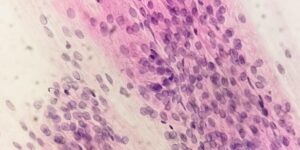

If you think you may have trich, your provider will collect a sample using vaginal discharge. Your provider may be able to confirm the presence of the microscopic parasite using a microscope, or they may send it to a lab for further testing.